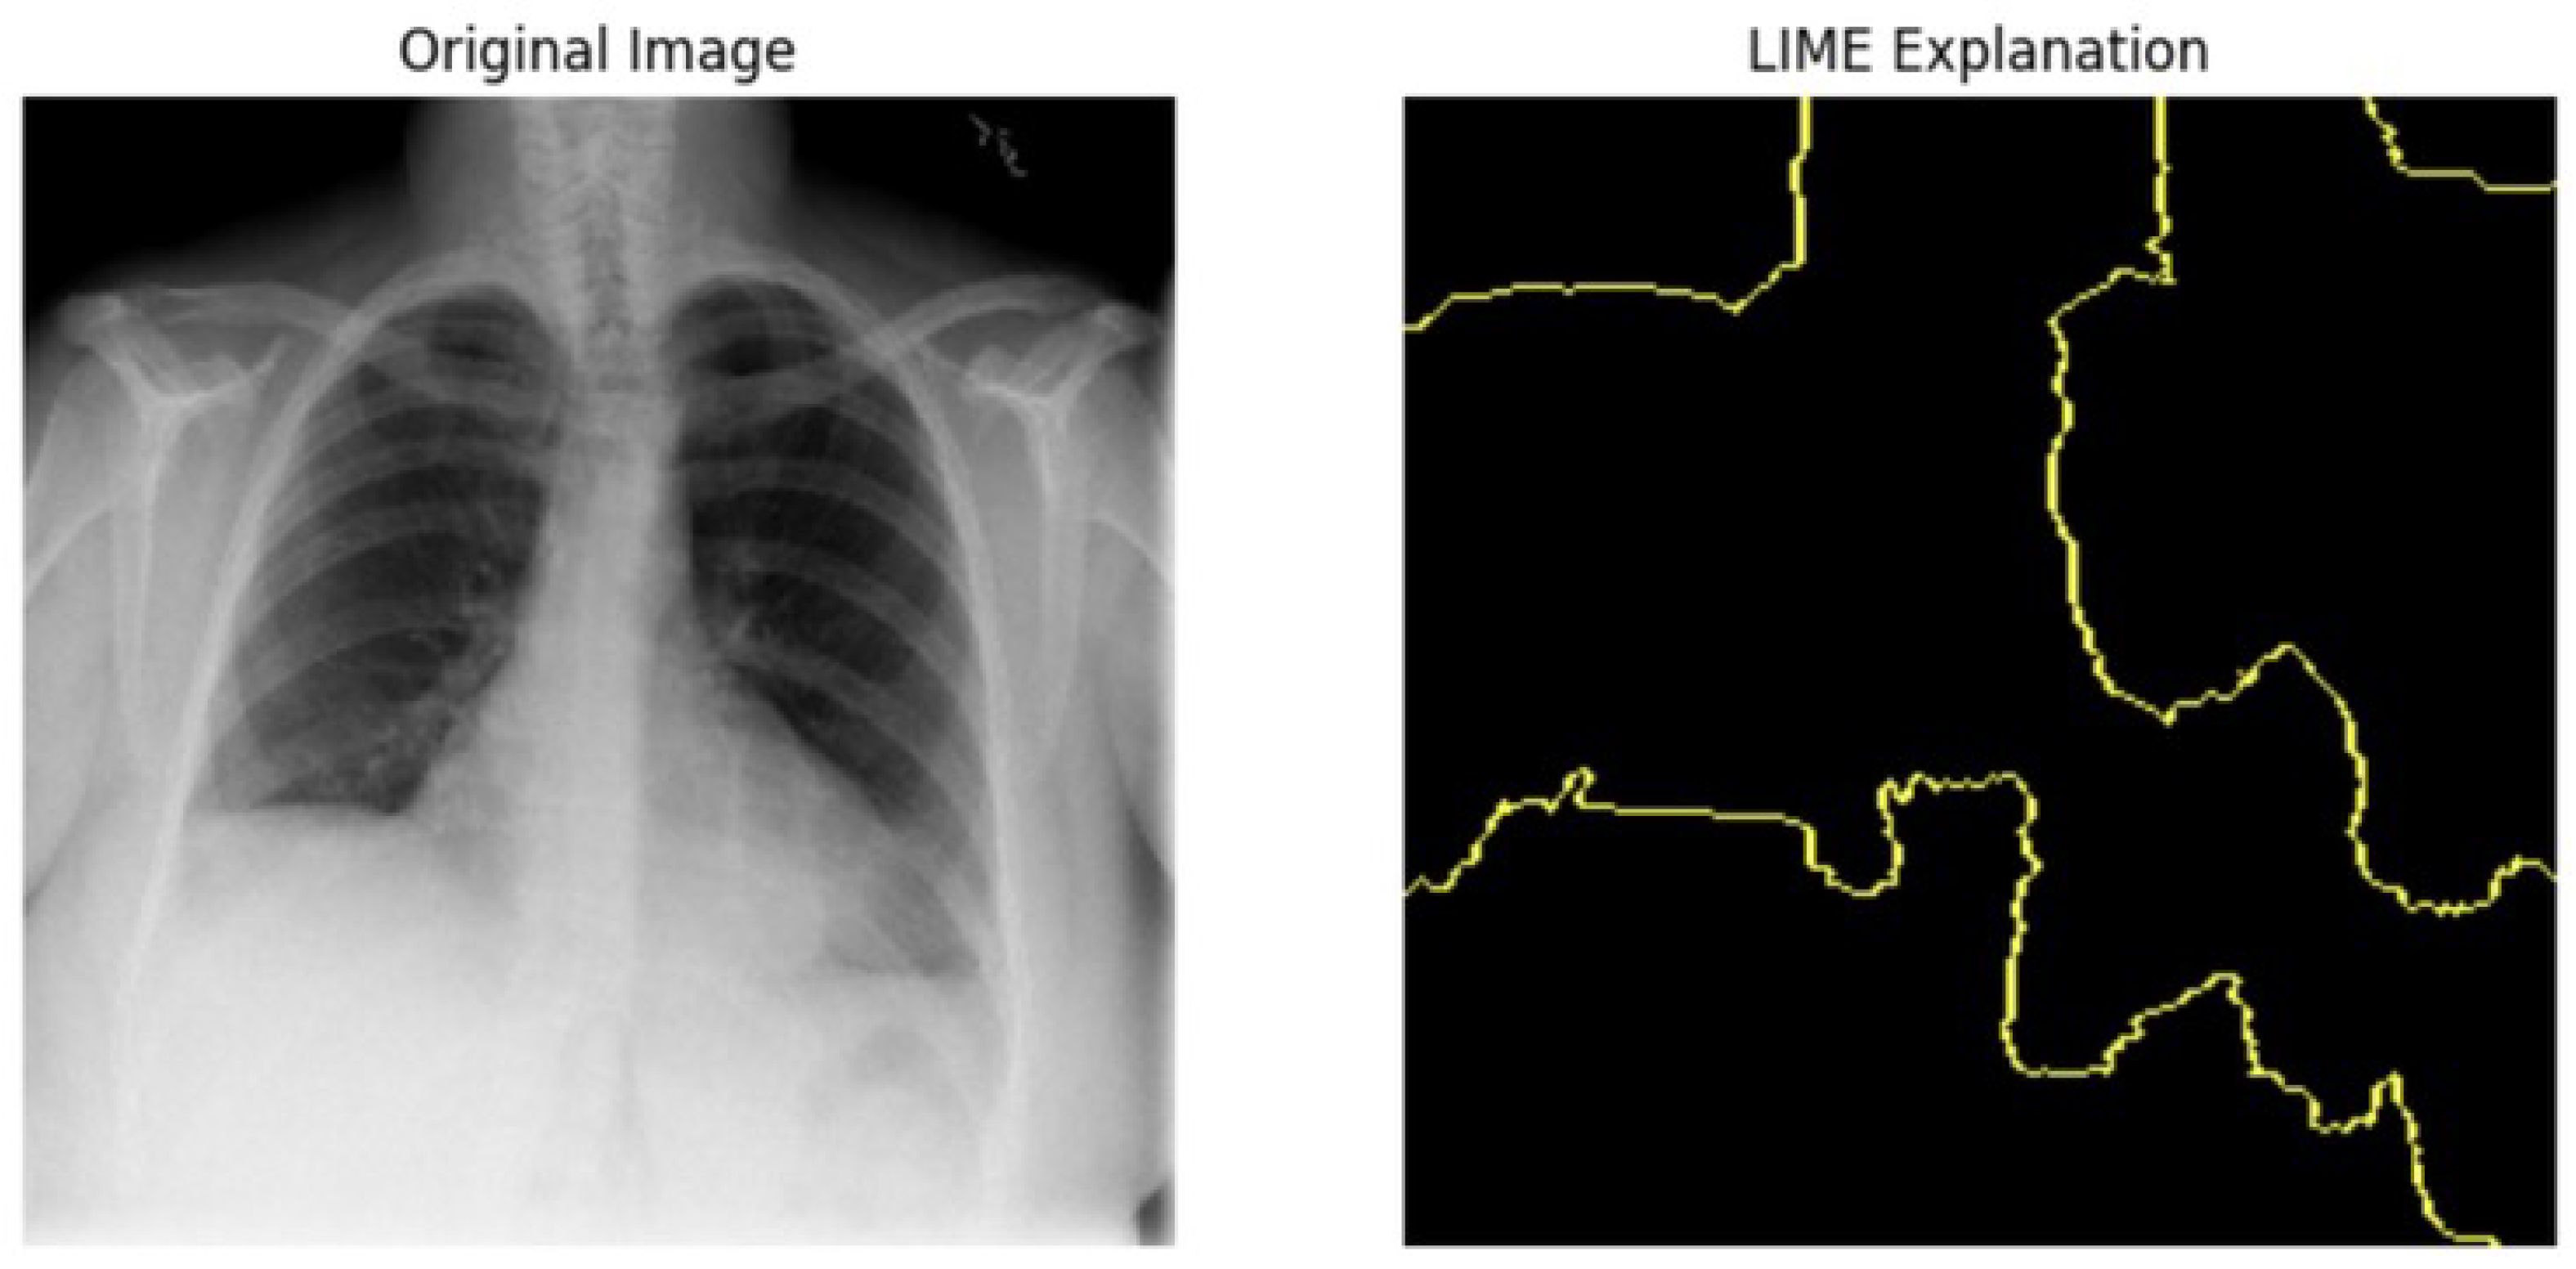

5.4.1. Local Interpretable Model-Agnostic Explanations for Clinical Validation

We applied scientific analysis on a random 7 sample, which was provided by the clinical specialist. The LIME Analysis for Image Data (a), (b), (c), (d), (e), and (f) is in Figure 22, Figure 23, Figure 24, Figure 25, Figure 26 and Figure 27. There are two parts of LIME analysis from the provided chest X-ray images to detect the disease area. Original Image and LIME explanation;

• Original Image: The patient’s thoracic cavity. It displays the typical anatomical structures of the chest, including the lungs, ribs, and heart.

• LIME Explanation: The result of applying LIME to the chest X-ray image. The yellow boundaries indicate the regions of the image that were most influential in the model’s decision-making process when determining whether the image indicated a particular condition. In this context, these regions are the parts of the X-ray that the AI model considered most important for making its diagnostic prediction.

The analysis very useful for clinicians to understand the model’s behavior and ensure that it aligns with medical expertise. The use of LIME helps in making the AI model’s interpretability decisions more transparent and interpretable. It allows medical professionals to verify whether the AI’s focus areas correspond to clinically significant regions. It also enhanced diagnostic capability of understanding which parts of the images in the AI model in refining the model further and ensures that it makes accurate and reliable predictions. This is particularly crucial in medical diagnostics where interpretability and accuracy are paramount.

Figure 23. LIME Analysis for Image Data (b) on original image to LIME explanation.

Jpm 14 00856 g023